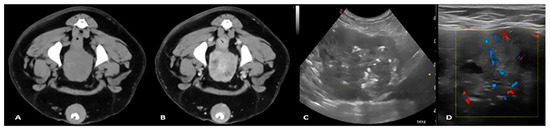

Imaging of Testicular Tumours